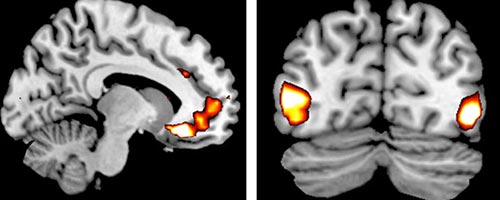

Carriers of a genetic variation (the ADRA2b deletion variant) showed more vivid perceptions of emotional events (called emotionally enhanced vividness or EEV), which was associated with more activity in a region of the brain responsible for regulating emotions and evaluating pleasure and threat (the ventromedial prefrontal cortex), researchers reported in the April 22 Journal of Neuroscience.

The 2014 study was a relatively small one, with 39 subjects undergoing fMRI scans at the University of Toronto. Slightly more than half (21) carried the ADRA2b deletion variant, and the rest did not. But the result was clear. Some people are genetically wired, as the researchers report, to “enhance the subjective vividness of perceptual experience and its emotional enhancement.”